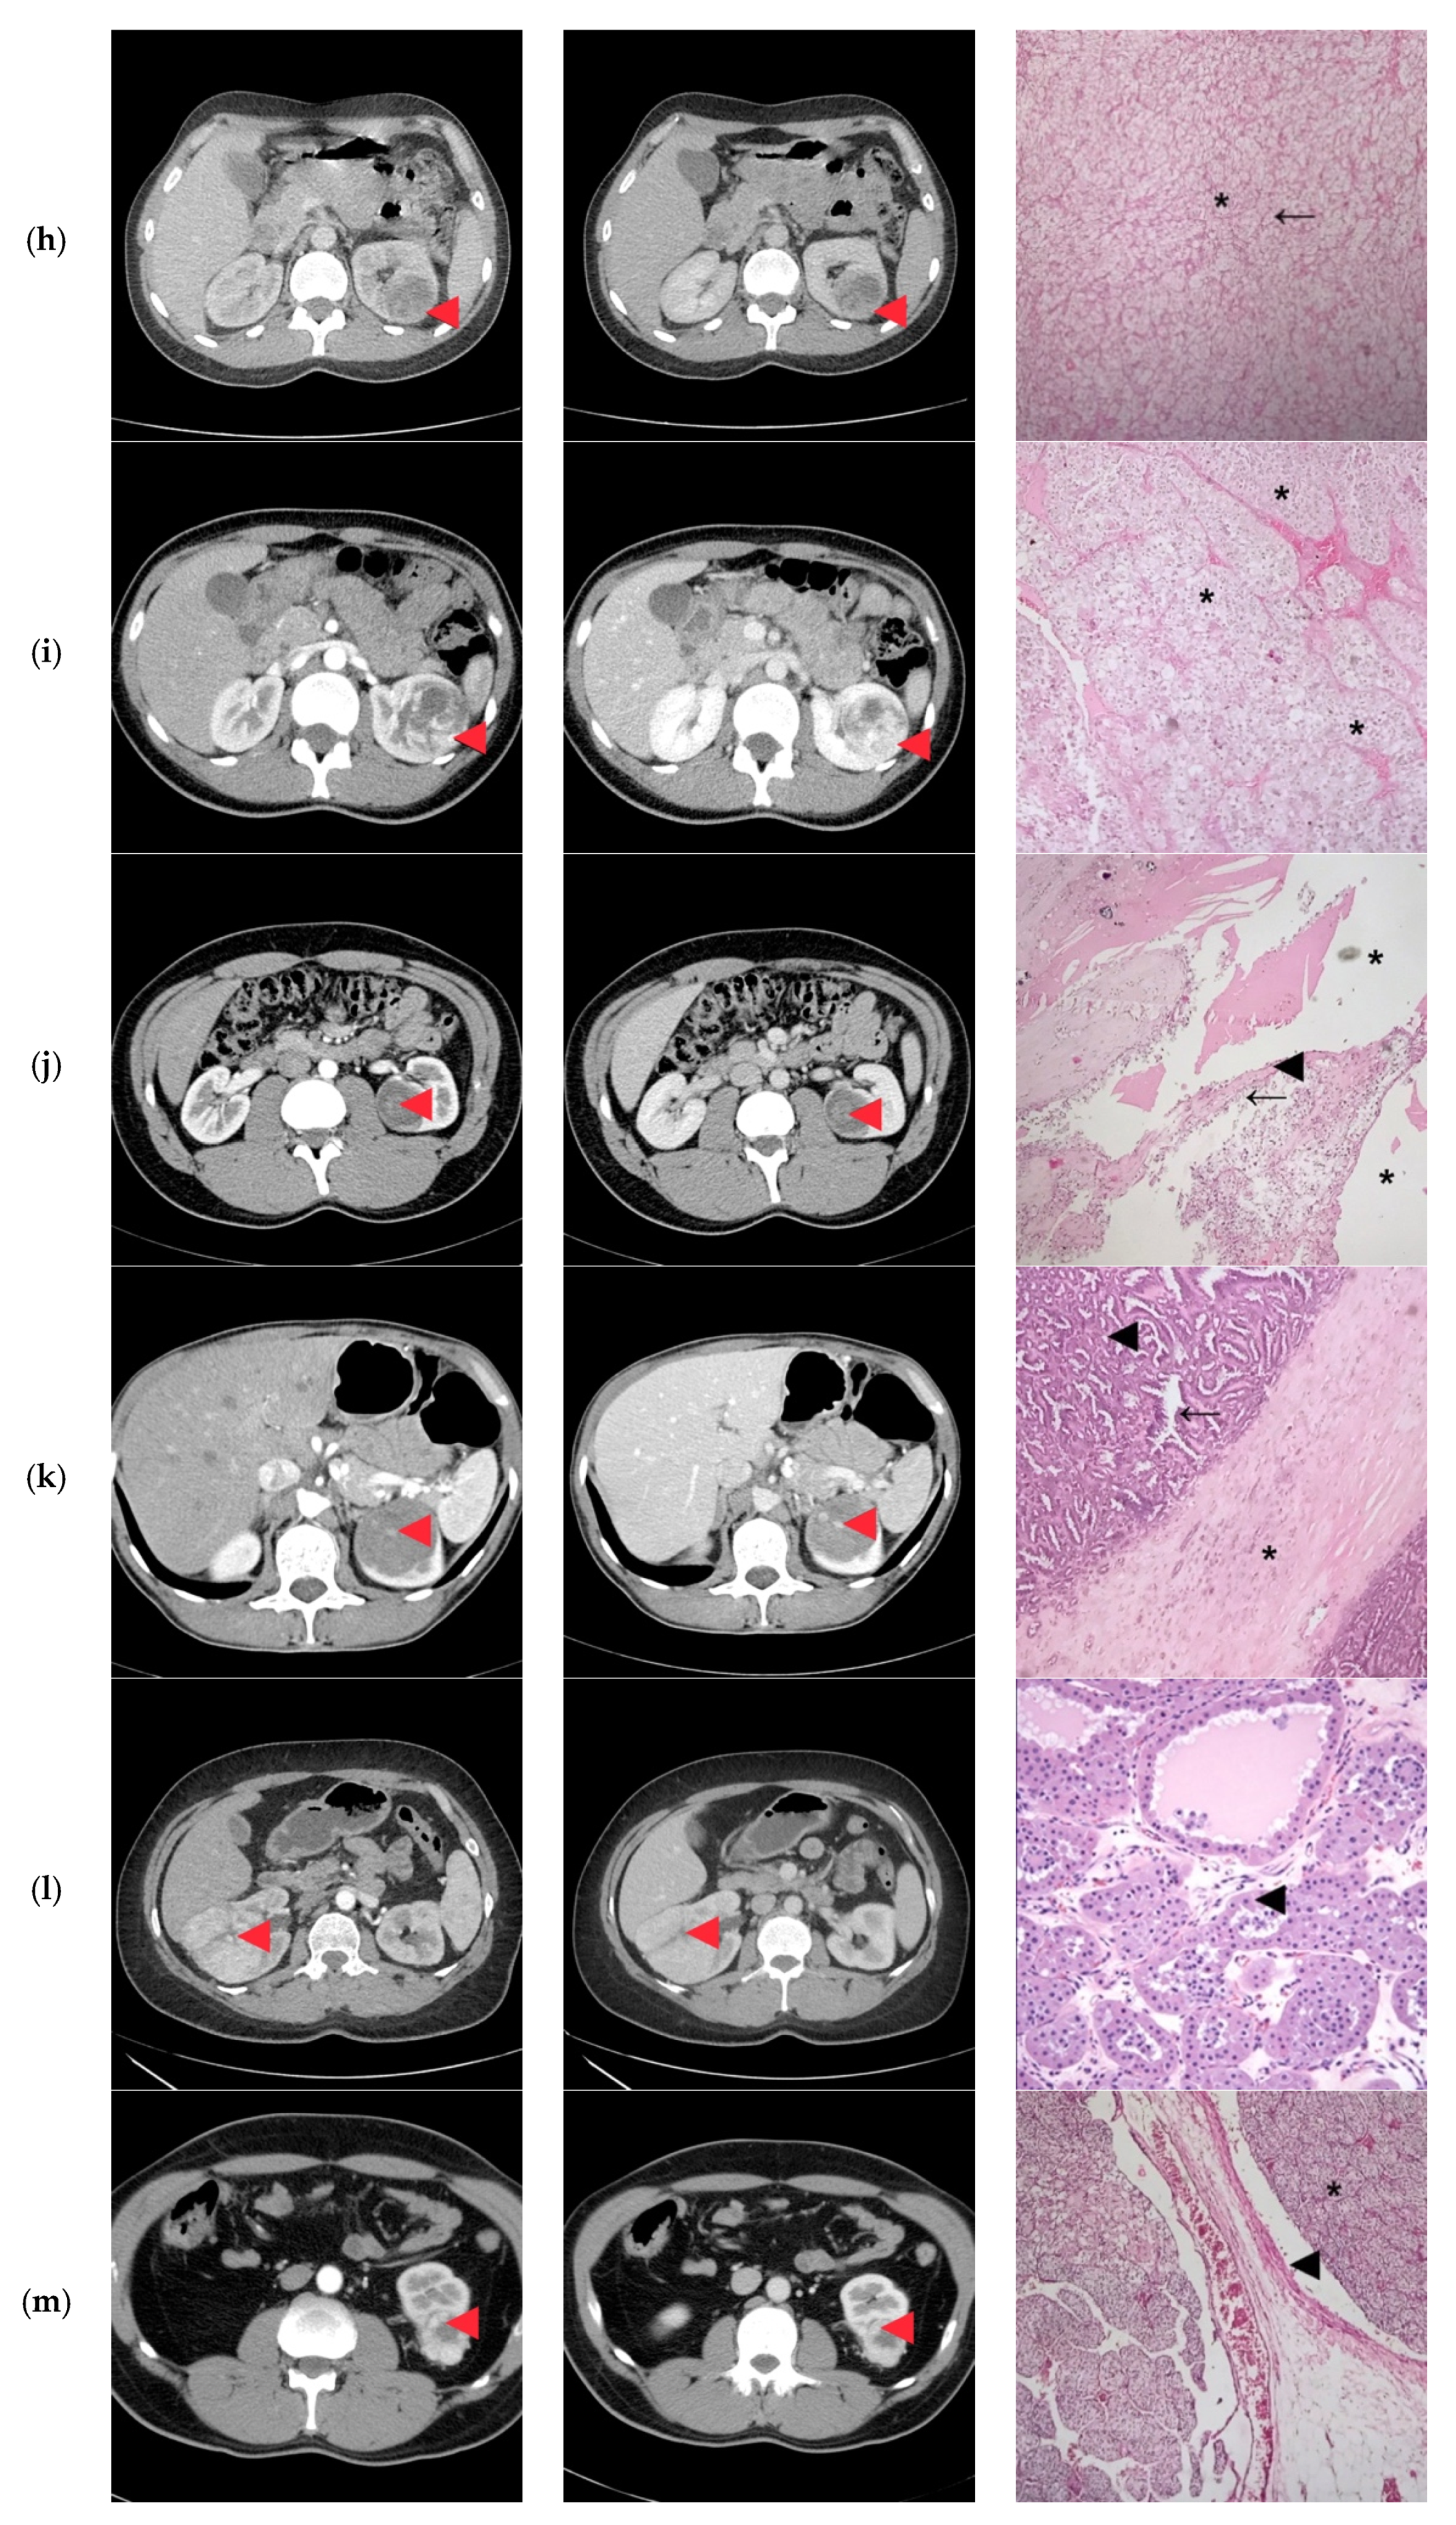

| 1 | 45/M | cT2N0 | 73 | 9 | Clear Cell RCC |

| 2 | 27/F | cT1bN0 | 60 | 8 | Clear Cell RCC |

| 3 | 38/M | cT1bN0 | 47 | 10 | Papillary/Clear Cell RCC Oncocytoma |

| 4 | 24/M | cT2N0 | 85 | 10 | Clear Cell RCC |

| 5 | 31/F | cT1aN0 | 35 | 8 | Papillary Clear Cell RCC |

| 6 | 41/M | cT2N0 | 86 | 10 | Clear Cell RCC |

| 7 | 29/M | cT1bN0 | 40 | 8 | Oncocytoma |

| 8 | 30/F | cT1bN0 | 44 | 10 | Papillary/Clear Cell RCC |

| 9 | 32/F | cT1bN0 | 52 | 11 | Clear Cell RCC |

| 10 | 25/M | cT1bN0 | 45 | 11 | Papillary/Clear Cell RCC Complicated cyst Oncocytoma/Fat poor AML |

| 11 | 43/F | cT1bN0 | 50 | 9 | Papillary RCC/Oncocytoma Fat poop AML |

| 12 | 41/F | cT2N0 | 73 | 10 | Oncocytoma |

| 13 | 43/M | cT3aN0 | 33 | 7 | Clear Cell RCC |

| 14 | 38/F | cT1bN0 | 50 | 8 | Bleeding Clear Cell RCC |

| 15 | 32/M | cT3aN0 | 55 | 10 | Clear Cell RCC |

| 16 | 37/M | cT2N0 | 93 | 11 | Clear Cell RCC |

| 1 | Retroperitoneoscopic radical nephrectomy | pT2N0 | Clear Cell RCC Furhman 2 | Yes |

| 2 | Open radical nephrectomy | pT1bN0 | Clear Cell RCC Furhman 1 | Yes |

| 3 | Retroperitoneoscopic radical nephrectomy | pT1bN0 | Papillary-RCC, type II | Yes/No |

| 4 | Open Radical nephrectomy | pT2N0 | Cystic Nephroma | No |

| 5 | Retroperitoneoscopic radical nephrectomy | pT1aN0 | Clear Cell RCC Furhman 1 | Yes/No |

| 6 | Open radical nephrectomy | pT2N0 | Clear Cell RCCFurhman 2 | Yes |

| 7 | Open partial nephrectomy with local renal hypothermia and hilar clamping | PT1bN0 | Multicentric Chromophobe-RCC | No |

| 8 | Open partial nephrectomy with local renal hypothermia and hilar clamping | pT1bN0 | Clear Cell RCC Furhman 1 | Yes/No |

| 9 | Retroperitoneoscopic radical nephrectomy | pT1bN0 | Clear Cell RCC Furhman 2 | Yes |

| 10 | Open partial nephrectomy with local renal hypothermia and hilar clamping | pT1bN0 | Multiloculated cystic Clear Cell RCC Furhman 1 | No |

| 11 | Open partial nephrectomy with local renal hypothermia and hilar clamping | pT1bN0 | Metanephric adenofibroma | No |

| 12 | Open radical nephrectomy | pT2N0 | Oncocytoma | Yes |

| 13 | Open partial nephrectomy–segmentary renal vein invasion–radical nephrectomy | pT3aN0 | Clear Cell RCC Furhman 1 | Yes |

| 14 | Open partial nephrectomy with local renal hypothermia and hilar clamping | pT1bN0 | Papillary-RCC, type I | No |

| 15 | Open radical nephrectomy | pT3aN0 | Clear Cell RCC Furhman 1 | Yes |

| 16 | Retroperitoneoscopic radical nephrectomy | pT2N0 | Clear Cell RCC Furhman 1 | Yes |